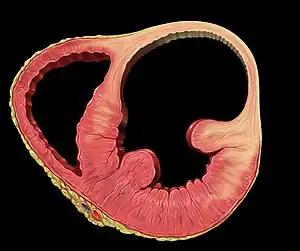

Ventricular aneurysms are one of the many complications that may occur after a heart attack. The word aneurysm refers to a bulge or 'pocketing' of the wall or lining of a vessel commonly occurring in the blood vessels at the base of the septum, or within the aorta. In the heart, they usually arise from a patch of weakened tissue in a ventricular wall, which swells into a bubble filled with blood.[1] This, in turn, may block the passageways leading out of the heart, leading to severely constricted blood flow to the body. Ventricular aneurysms can be fatal. They are usually non-rupturing because they are lined by scar tissue.

Ventricular aneurysms usually grow at a very slow pace, but can still pose problems. Usually, this type of aneurysm grows in the left ventricle. This bubble has the potential to block blood flow to the rest of the body, and thus limit the patient's stamina. In other cases, a similarly developed pseudoaneurysm ("false aneurysm") may burst, sometimes resulting in the death of the patient. Also, blood clots may form on the inside of ventricular aneurysms, and form embolisms. If such a clot escapes from the aneurysm, it will be moved in the circulation throughout the body. If it gets stuck inside a blood vessel, it may cause ischemia in a limb, a painful condition that can lead to reduced movement and tissue death in the limb.[1] Alternatively, if a clot blocks a vessel going to the brain, it can cause a stroke. In certain cases, ventricular aneurysms cause ventricular failure or arrythmia. At this stage, treatment is necessary.

Ventricular aneurysms are usually complications resulting from a heart attack. When the heart muscle (cardiac muscle) partially dies during a heart attack, a layer of muscle may survive, and, being severely weakened, start to become an aneurysm. Blood may flow into the surrounding dead muscle and inflate the weakened flap of muscle into a bubble. It may also be congenital.